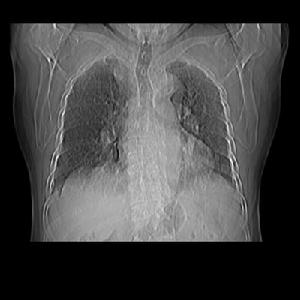

2、心電圖檢查 心電圖變化由急性右心室擴張所致,常示電軸顯著右偏,極度順鐘向轉位。I導聯S波深、ST段呈J點壓低,Ⅲ導聯Q波顯著和T波倒置,呈SⅠQⅢTⅢ波型。aVF和Ⅲ導聯相似,aVR導聯R波常增高,右胸導聯R波增高、T波倒置。P波高而尖呈肺型P波。可出現房性或室性心律失常。上述變化大部分數天后恢復。肺梗死本身一般不引起心電圖改變。